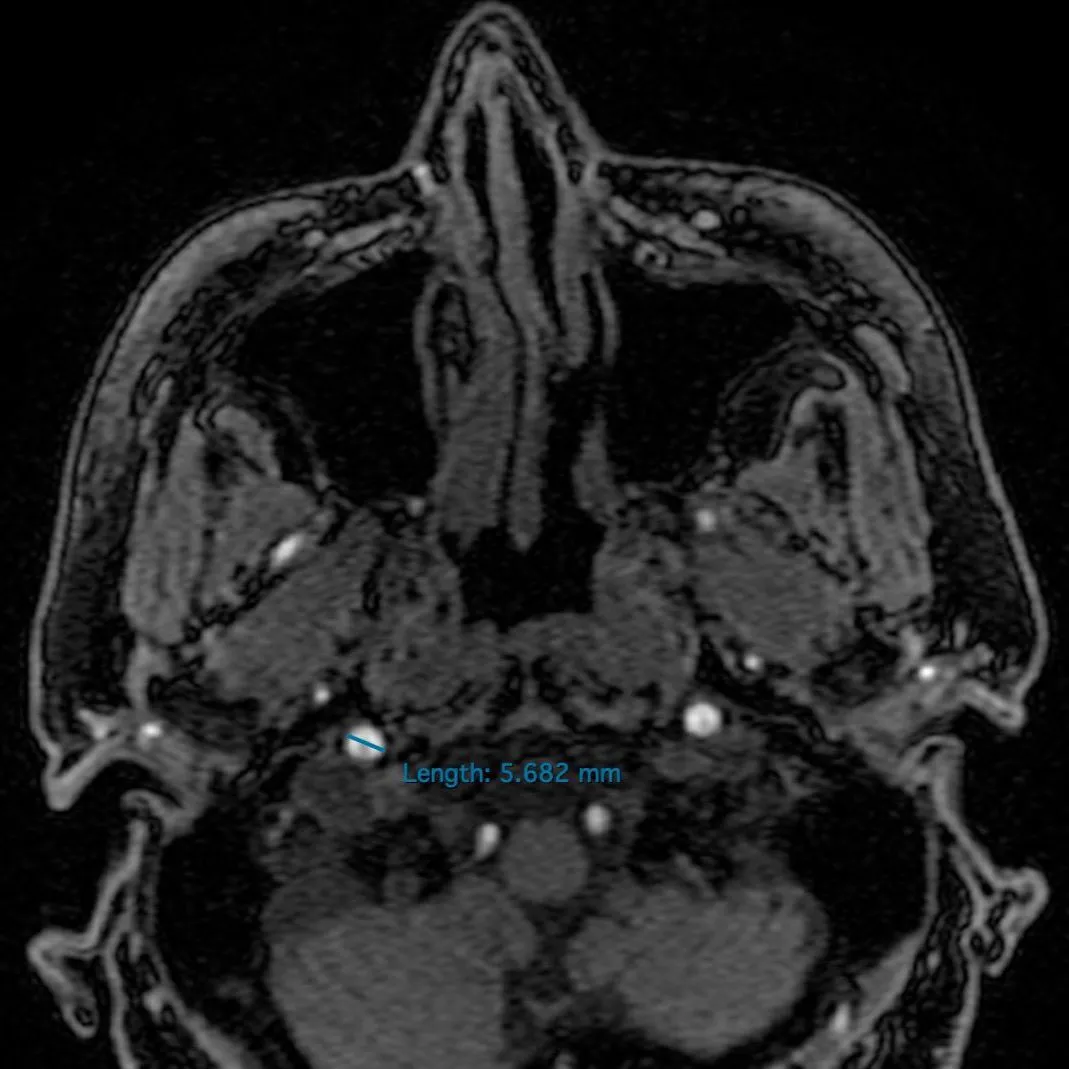

Ölçüm

MRA Ölçüm